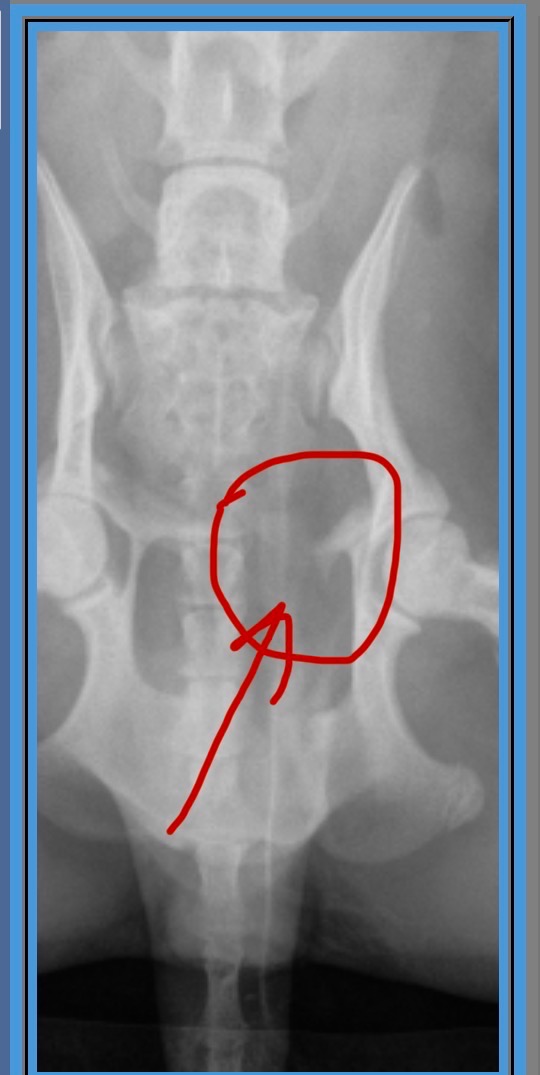

This morning, what was meant to be a joyful day celebrating Christmas with our family turned into a heartbreaking nightmare. Our sweet little dog, Canela, suffered a terrible accident when two heavy celebration tables fell on top of her. The impact caused two fractures in her pelvis, and she was rushed to the emergency veterinary hospital. Canela is currently hospitalized, in pain, and waiting for urgent surgery.